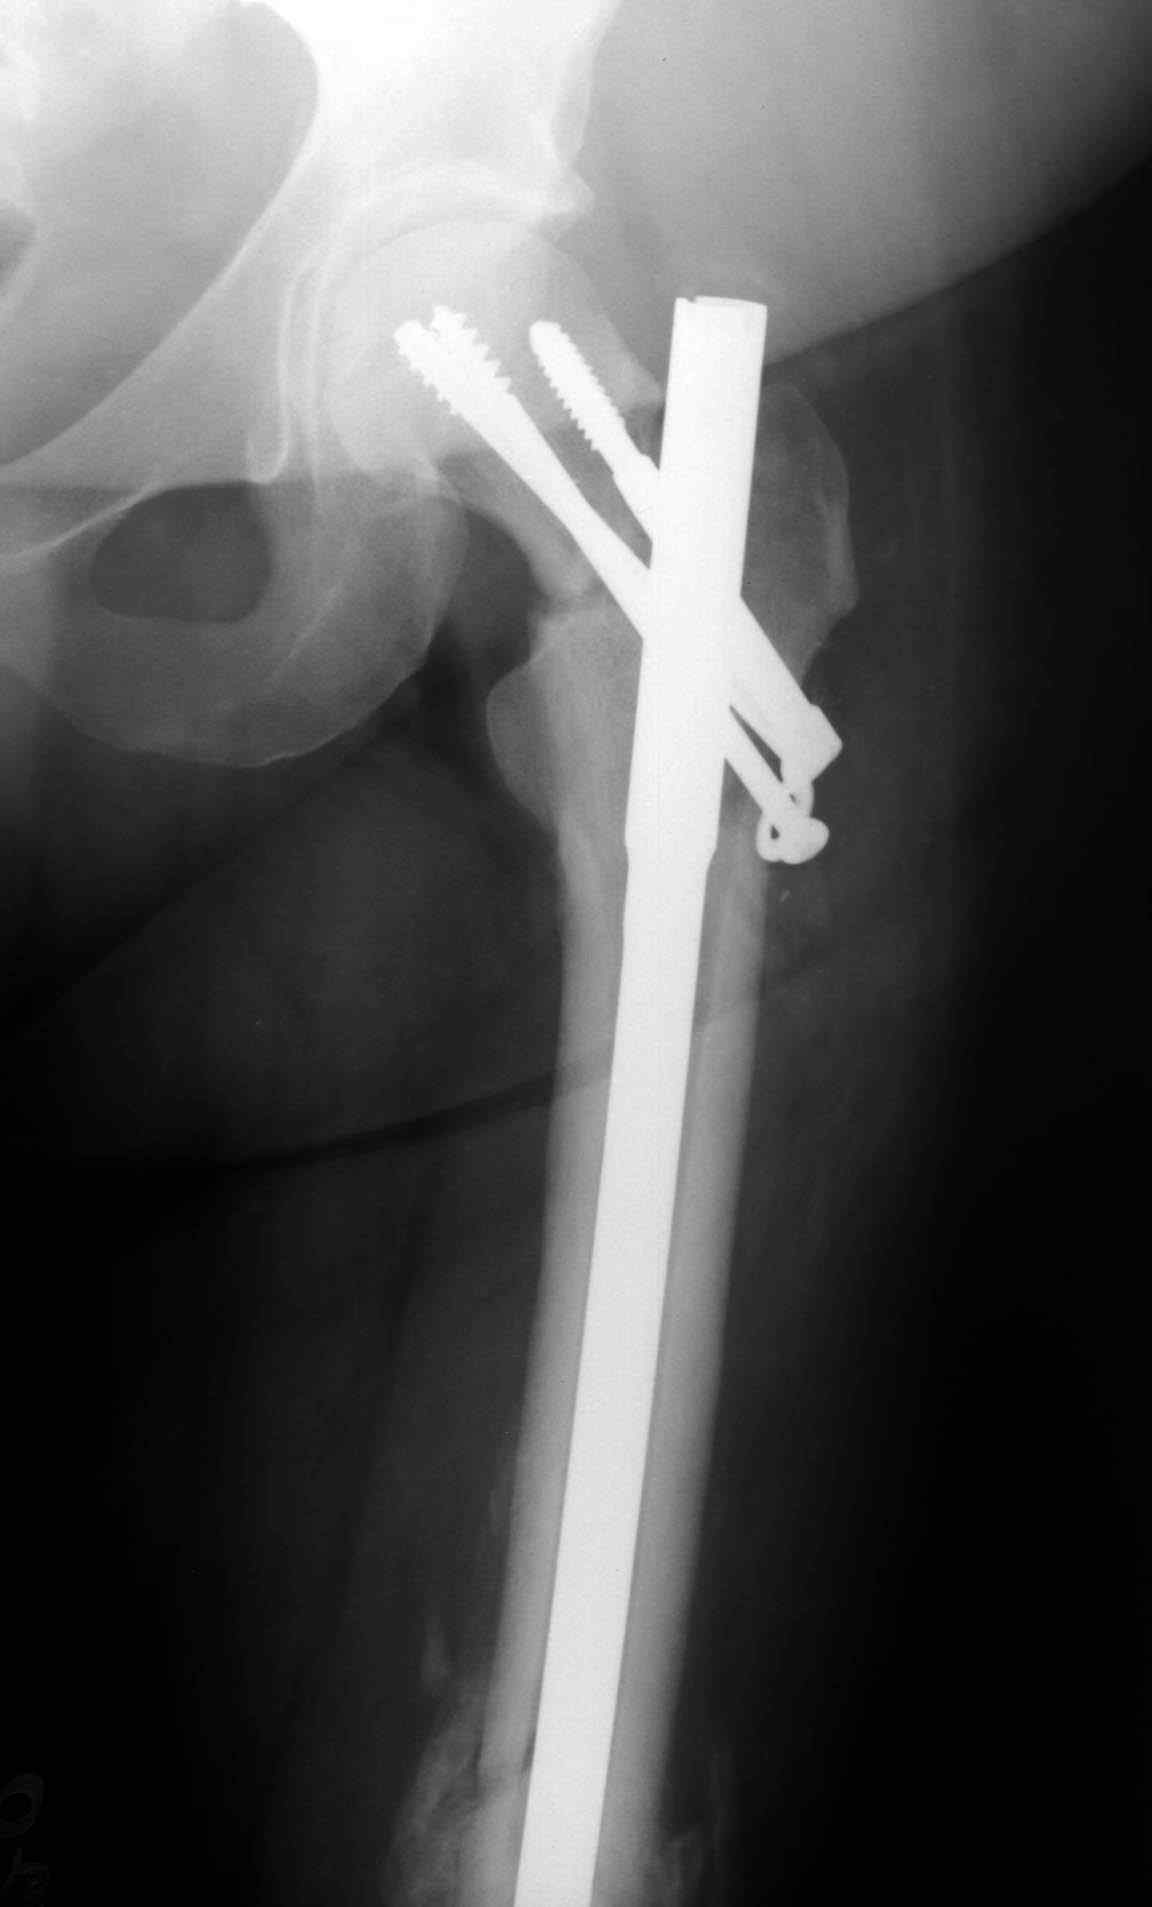

Уважаемые коллеги. Благодарим за дискуссию. Мы решили выполнить комбинированную операцию - эндопротезирование тазобедренного сустава и ретроградный интрамедуллярный остеосинтез (одномоментно)

This is very bad situation. To miss fracture subcapital like this is unforgivable. Now the fracture of the femoral shaft isn't healed with malreduction component and fracture of the subcapital femur (doesn't matter what grade) without any chance for healing. More of them, therк is very high chanse to AVN of the femoral head. At the moment nothing can be done exept change of the intramedullary nail in femoral shaft

with femoral neck fixation after open reduction . I mean PF Aesculap nail or TAN Smith & Nerphuy). After that waiting with hoope to union of the femoral shaft fracture and, depending on condition of the femoral head, in the life - suprise, or go to THR noncemented if the head will be dead. Any way this young man is invalid. Good luck !

А открытая репозиция шейки окончательно не лишит кровоснабжения головку? Не говоря о технической сложности вальгизации проксимального отдела бедра при фиксации гвоздем.

Наверно, вариант с вальгизирующей остеотомией с фиксацией blade plate или DHS более щадящий. А диафиз можно рефиксировать ретроградно. Или про эндопротезирование с очень длинной ножкой подумать.